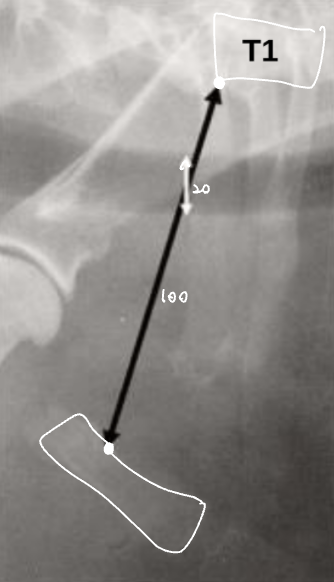

Tracheal diameter ์ฌ๋ ๋ฒ๋ฒ

- Thoracic inlet๊ณผ์ ๋น์จ๋ก ๋ํ๋ธ๋ค.

![]() | - T1์ ๋๋ถ๋ถ์์, 1๋ฒ sternum์ ๊ฐ์ฅ ์ค๋ชฉํ ๋ถ๋ถ (Thoracic inlet)์ ์ ์ผ๋ก ์๊ณ ๊ธธ์ด๋ฅผ ์ฐ๋ค. - Trachea์ ๊ธธ์ด๋ฅผ ์ฐ๋ค. - ๋น์จ์ ๋ณดํต 0.2 ์ ๋. ![]() (๋จ๋์ข ์์๋ ์ ์์ ์ผ๋ก ๋ ์๋ค.) |